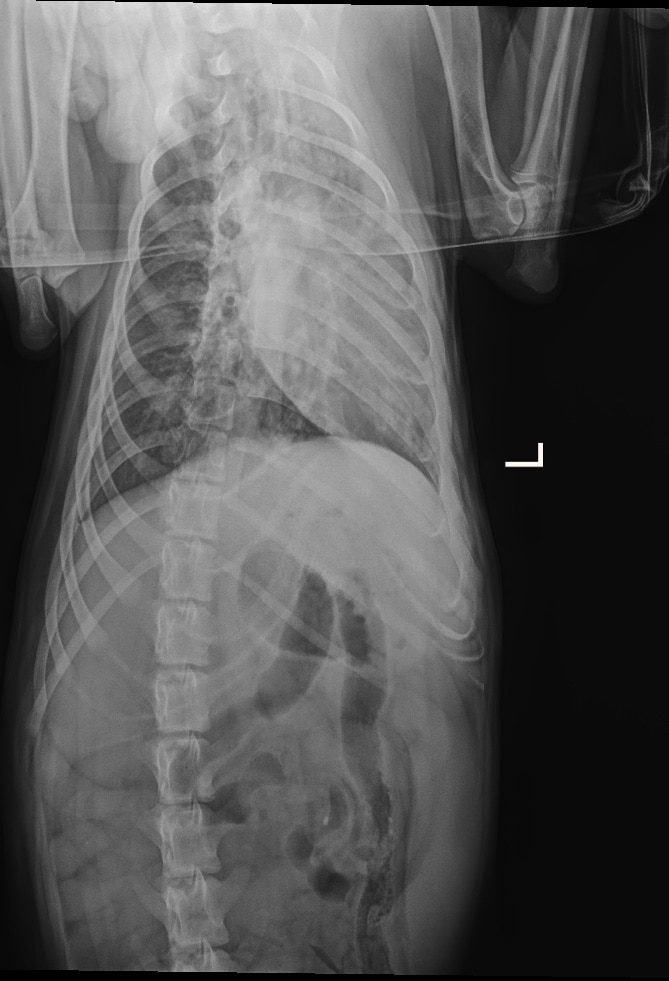

FENRIK ist ein wunderbarer, toller Hund, freundlich, liebenswert und einfach ein toller Gefährte. Leider bringt er gesundheitliche Probleme mit, die nicht zu unterschätzen sind. Laut unserer Tierärztin handelt es sich bei ihm um einen medizinischen Notfall. Bereits als Welpe hatte FENRIK wiederholt mit Lungenerkrankungen zu kämpfen. Es ist daher wahrscheinlich, dass seine Lunge dauerhaft geschädigt sein könnte oder dass er zumindest immer wieder anfällig für Lungenentzündungen bleibt.